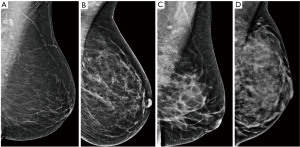

The performance of mammography is dependent on the breast density, which is determined by the proportion of glandular parenchyma and fat. The density is scored by the BI-RADS system from A (fatty) to D (dense) (Figure 2) and the sensitivity of mammography varies accordingly. In fatty breasts almost no cancer goes undetected, while in dense breasts the sensitivity can drop down to 50% (19). High breast density is an independent risk factor for breast cancer (20) and is also associated with higher proportion of interval cancers as smaller cancers can be masked by the dense parenchyma during screening (21). The density tends to change during life, decreasing with age. Mammography is therefore used and is more efficient in women over 40 years of age (22).